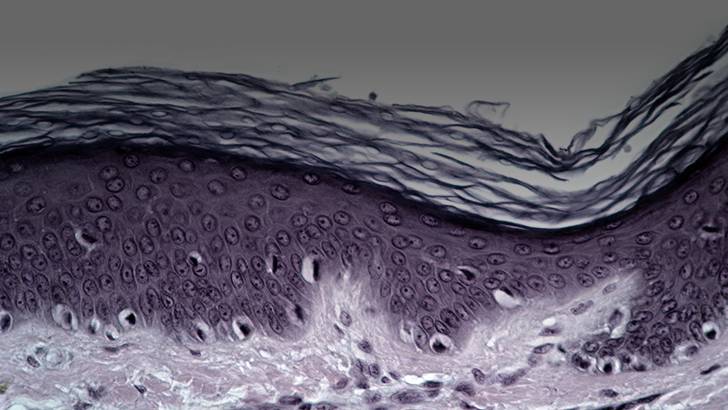

Yeah, so that was kind of the key advance that we found in 2015’s manuscript, was basically our material, by making these individual beads anneal together in the tissue, it allowed cells to go into the hydrogel and into the tissue. It sort of acted like our body’s own tissue, and it was, as Dr. Segura pointed out, immune stealth. So it was interesting when I looked at the pathology of the skin, because I’m a dermatopathologist as well, I saw something very interesting. Number one, the D amino acid hydrogel, the mirror image hydrogel, did not have any hydrogel in the tissue, whereas the L amino acid hydrogel, the normal one, did. So, there was a very large difference because number one, there was no hydrogel there anymore. But what was really exciting to me, looking at the pathology of the skin, we didn’t see the typical appearance of scars in the tissue that had the D hydrogel implanted. In a scar, what we typically see is that the surface or the epidermis as we call it, which is a few cell layers thick, usually very flat, and then you have in the dermis, the layer of skin underneath that feeds the epidermis. You have parallel blood vessels, so the blood vessels go perpendicular to the skin, and they’re all very interspersed and arranged in a scar. The collagen bundles of the dermis are basically all very flat, and you lose undulation of collagen fibers. We didn’t see that in the skin samples treated with the hydrogel that had D peptides. It looked more like normal skin, and we saw hair follicles and sebaceous glands forming directly in the wound bed. Now there is a wound model called wound-induced hair neogenesis, where this happens spontaneously in very, very large wounds in mice. But in the small wound model that we used, I was used to only seeing scar as the end result. So, that’s what was really exciting was in these small wounds that we were creating; we were able to see a completely new phenotype, where the hydrogel led to regenerated skin in a model where we don’t typically see hair regeneration.